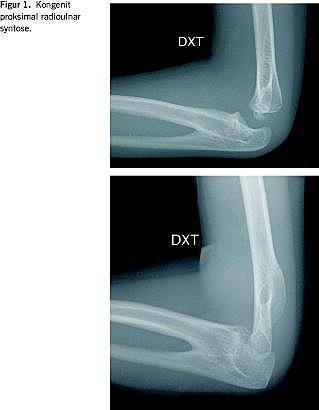

En synostose mellem den proksimale del af radius og ulna er en sjældent forekommende udviklingsabnormitet, som sopstår som følge af en mislykket segmentation mellem radius og ulna (Figur 1 ).